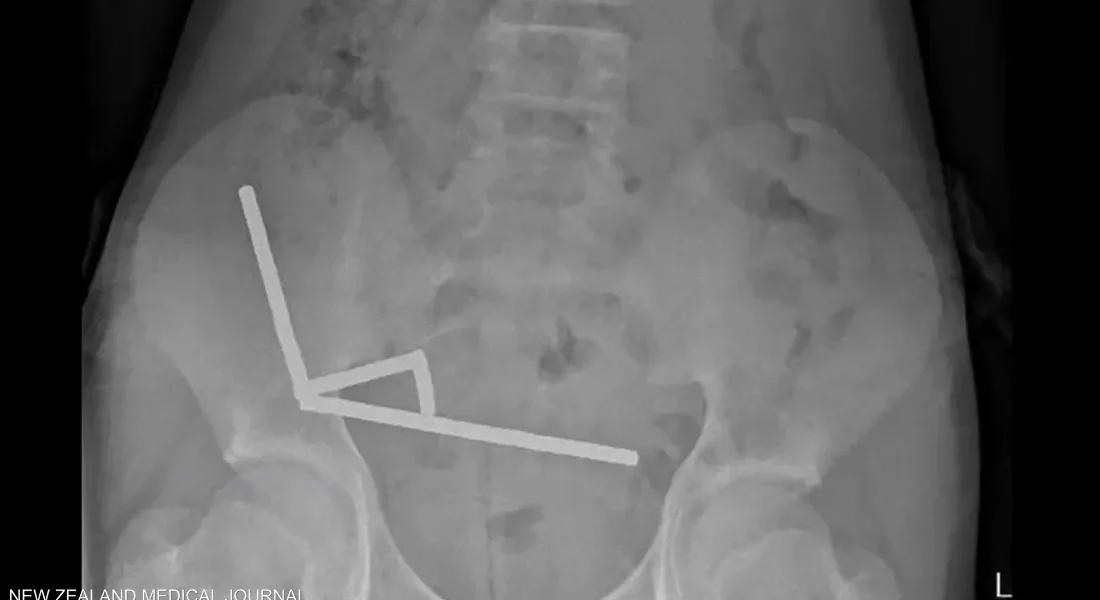

وأظهرت صور الأشعة أن القطع المغناطيسية تكتلت داخل أمعائه في أربعة خطوط مستقيمة، والتصقت ببعضها البعض عبر القوى المغناطيسية، ما أدى إلى تلف في أنسجة الأمعاء الدقيقة والغليظة. وأكد الأطباء أن الضغط الناتج عن المغناطيس تسبب في موت أجزاء من الأنسجة، مما استدعى إجراء جراحة عاجلة لإزالتها.